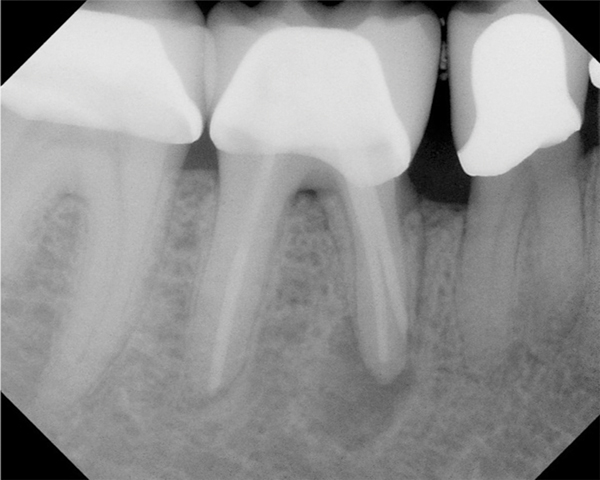

Figure 11. Preoperative radiograph. Courtesy of Dr. Guillaume Jouanny.

Figure 11

Figure 12. Postoperative radiography after full pulpotomy was performed. Courtesy of Dr. Guillaume Jouanny.

Figure 12

Figure 13. Tooth was asymptomatic at 1-year follow-up. Courtesy of Dr. Guillaume Jouanny.

Figure 13

Figure 14. Contralateral tooth at 1-year follow-up. Courtesy of Dr. Guillaume Jouanny.

Figure 14